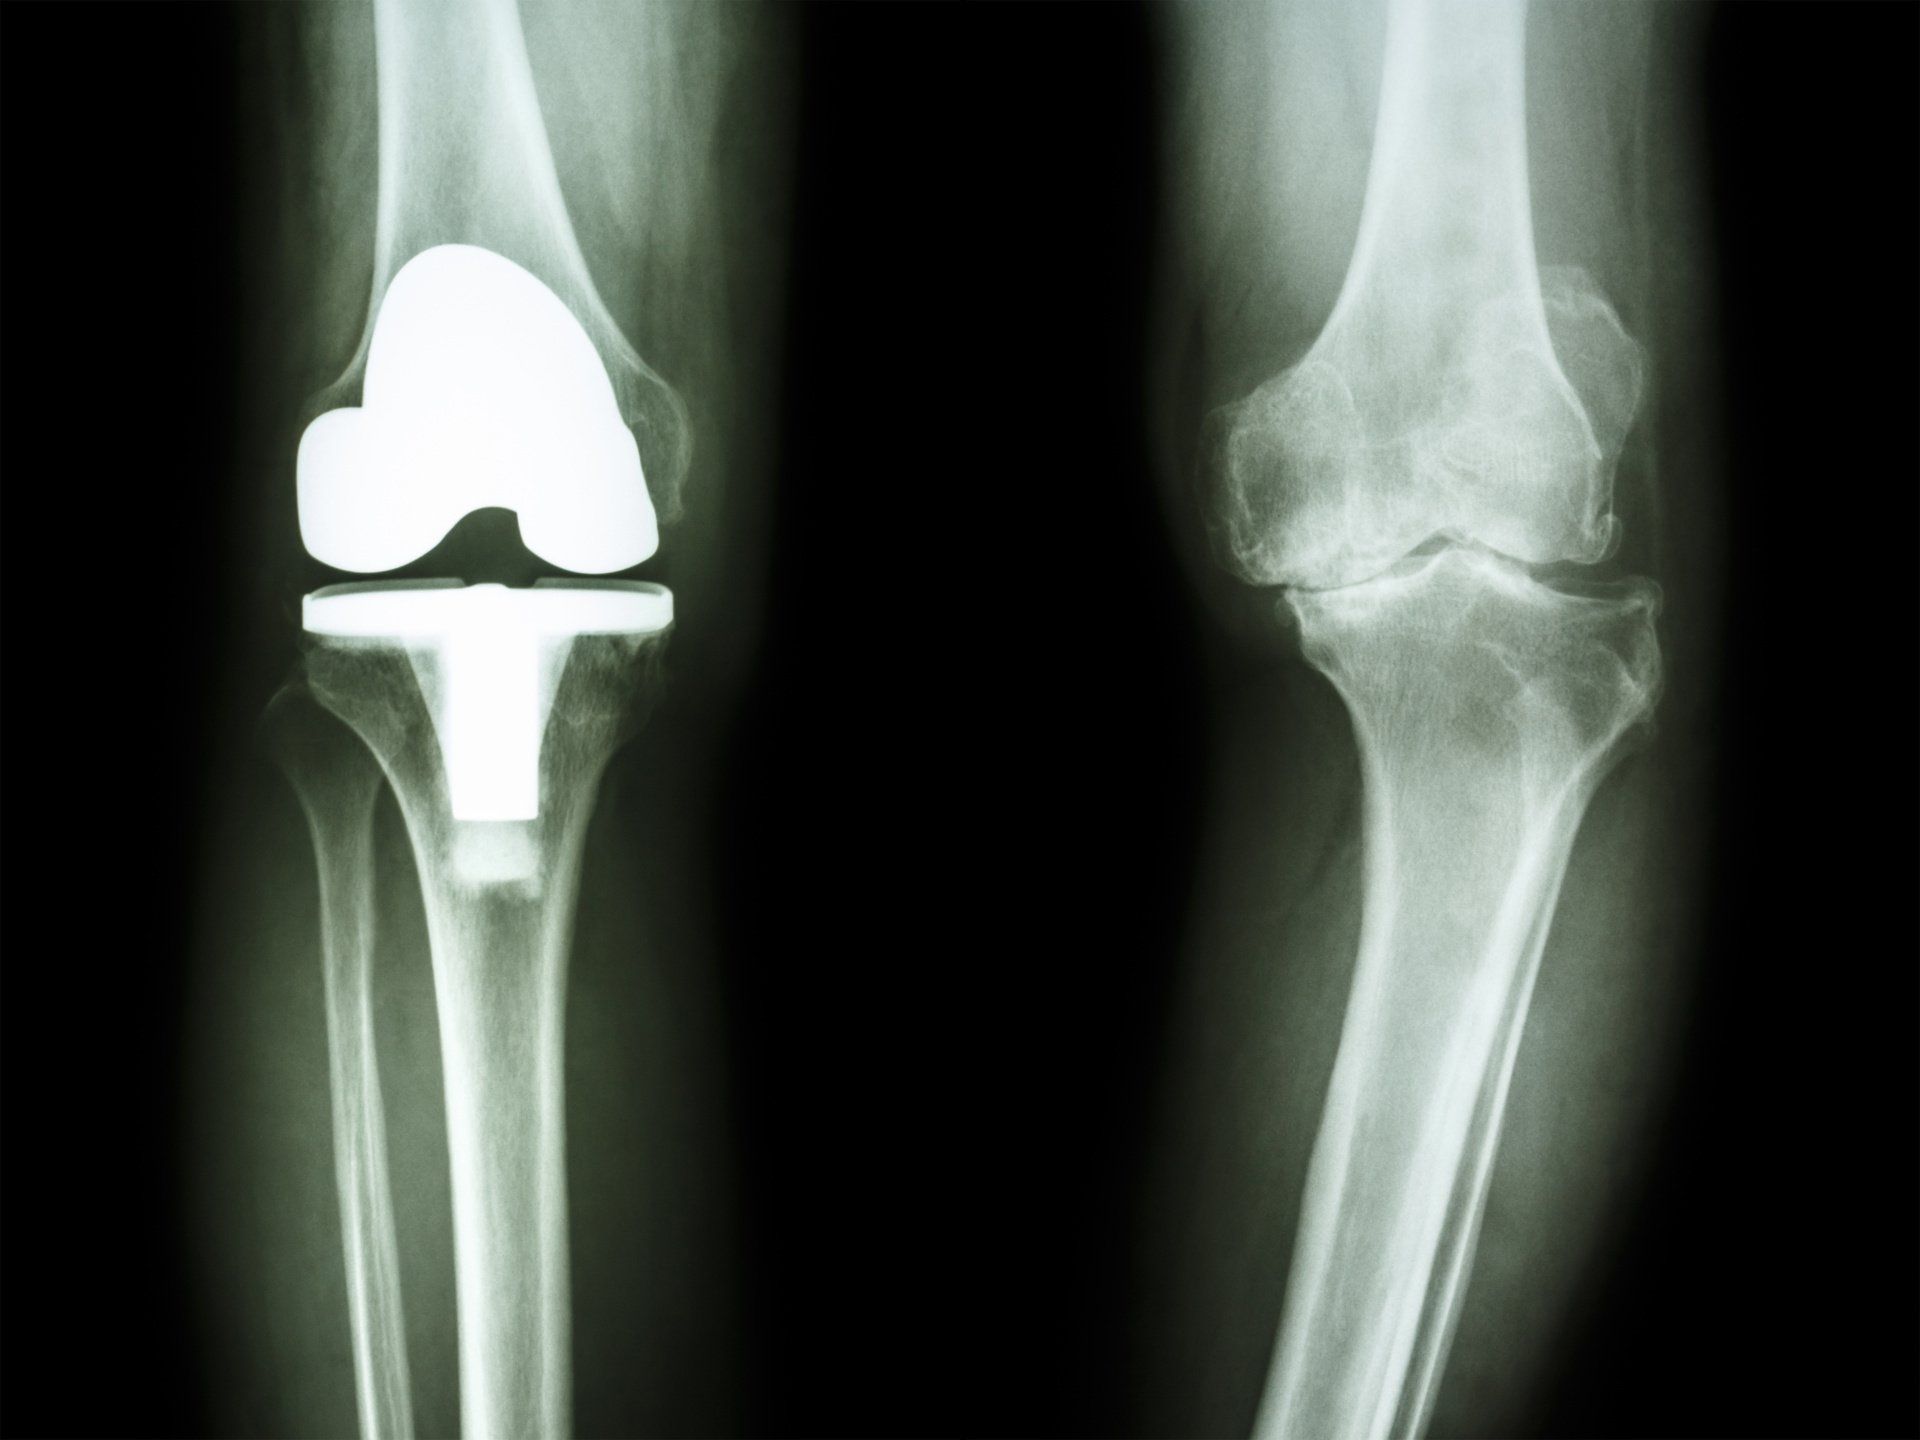

- Total Knee Replacement:

- Suitable when there is:

- Widespread symptomatic arthritis in the knee

- Failed non-surgical treatment options

- Involves replacing the worn-out joint surface of the knee with metal above and below, and plastic in between